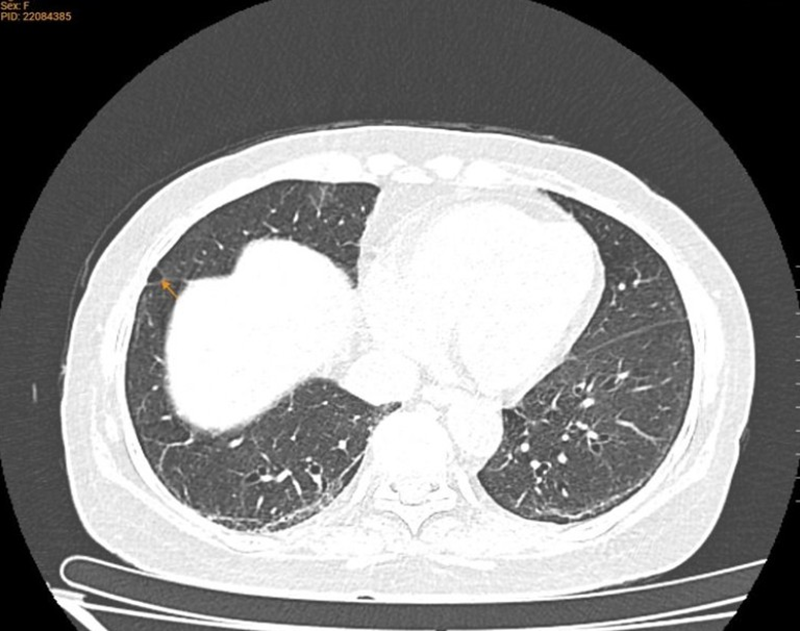

- Chụp CT phổi liều thấp: Giãn phế quản thùy dưới hai phổi; Dải xơ, dày tổ chức kẽ hai phổi (tổn thương cũ); Giãn phế nang thùy giữa phổi phải; Xơ vữa vôi hóa cung động mạch chủ; Thoái hóa cột sống ngực.

CT phổi cho thấy hình ảnh giãn phế nang thùy giữa phổi phải, giãn phế quản thùy dưới hai phổi, dải xơ, dày tổ chức kẽ hai phổi